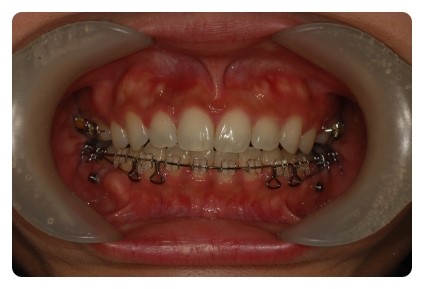

이번달에는 월치료 진료가 끝나고 원장쌤과

치아교정 전후 체크를 하며 상담시간을 가졌어요

치아교정 전후 사진을 비교해보니 쏘옥 들어간 앞니 ~~~

보다 더 놀라운건 교합 !!

상하악이 거의 맞물리고 잇엇는데

지금은 윗니가 아랫니를 싸악 ~~~ 덮는 이쁜 모양새 ~~~

덧니교정을 시작한지 벌써 2년이라며 징징대긴 햇지만

이뻐지고잇는 치아들을 보니 금새 기분좋아짐 ㅋㅋ